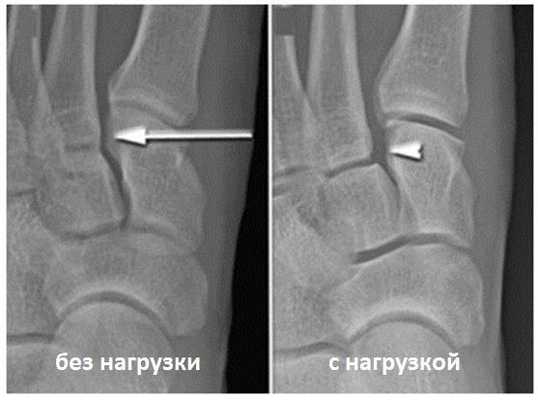

о Латеральное смещение основания 2-й плюсневой кости относительно промежуточной клиновидной кости:

- Может выявляться лишь при исследовании стопы с нагрузкой

- Результаты рентгенографии даже при исследовании с нагрузкой могут оказаться ложноотрицательными

3. Рентгенография при повреждении связки Лисфранка:

• Чувствительность рентгенографии повышается при исследовании стопы с нагрузкой (в положении пациента стоя или при наружной ротации стопы)

• Латеральное или дорсальное смещение основания 2-й плюсневой кости относительно промежуточной клиновидной кости

(Слева) На рентгенограмме, выполненной без нагрузки, не видно каких-либо признаков повреждения сустава Лисфранка. (Справа) На рентгенограмме в положении стоя мы видим увеличение расстояния между костями, свидетельствующее в повреждении связок сустава Лисфранка.

Для инструментальной диагностики используются рентгенограммы с\без нагрузки в сравнении со здоровой стороной, при их малой информативности рекомендовано выполнение стресс-рентгенограмм, аналогично приведёному выше тесту на нестабильность.

При рентгенографии все снимки выполняются в сравнении со здоровой стопой. Существует несколько основных рентгенологических признаков повреждения сустава Лисфранка. 1. Отсутствие параллельности медиального края основания 2-й плюсневой и медиального края медиальной клиновидной кости 2. Расширение между основаниями 1 и 2 плюсневых костей 3. Наличие костного фрагмента в области основания 2-1 плюсневой кости 4. Тыльный подвывих на боковой проекции 5. Разрыв линии предплюсне-плюсневого сочленения.

Вышеуказанные классификации относятся к переломовывихам, и вывихам в суставе Лисфранка, тяжёлым повреждениям, чаще встречающимся при высокоэнергетической травме, сопровождаемые значительным риском осложнений. Но во второй половине, особенно в конце XX века, в связи со значимым увеличением количества людей занимающихся спортом, возросла и частота низкоэнергетических повреждений сустава Лисфранка. В связи с чем Nunley & Vertullo в 2002 году предложили классификацию изолированных повреждений связки Лисфранка. Чаще всего они возникают при занятиях спортом и других низкоэнергетических травмах, и затрагивают только среднюю колонну стопы – 2-3 предплюсне-плюсневые суставы. Диагностика этих повреждений крайне сложна, так как рентгенологические признаки выявляются только при выполнении рентгенограмм с нагрузкой. Тем не менее это важная ортопедическая задача, так как повреждения 2-3 ст если оставить их не леченными часто приводят в последующем к хроническим болям в стопе и значительному ограничению уровня физической активности.